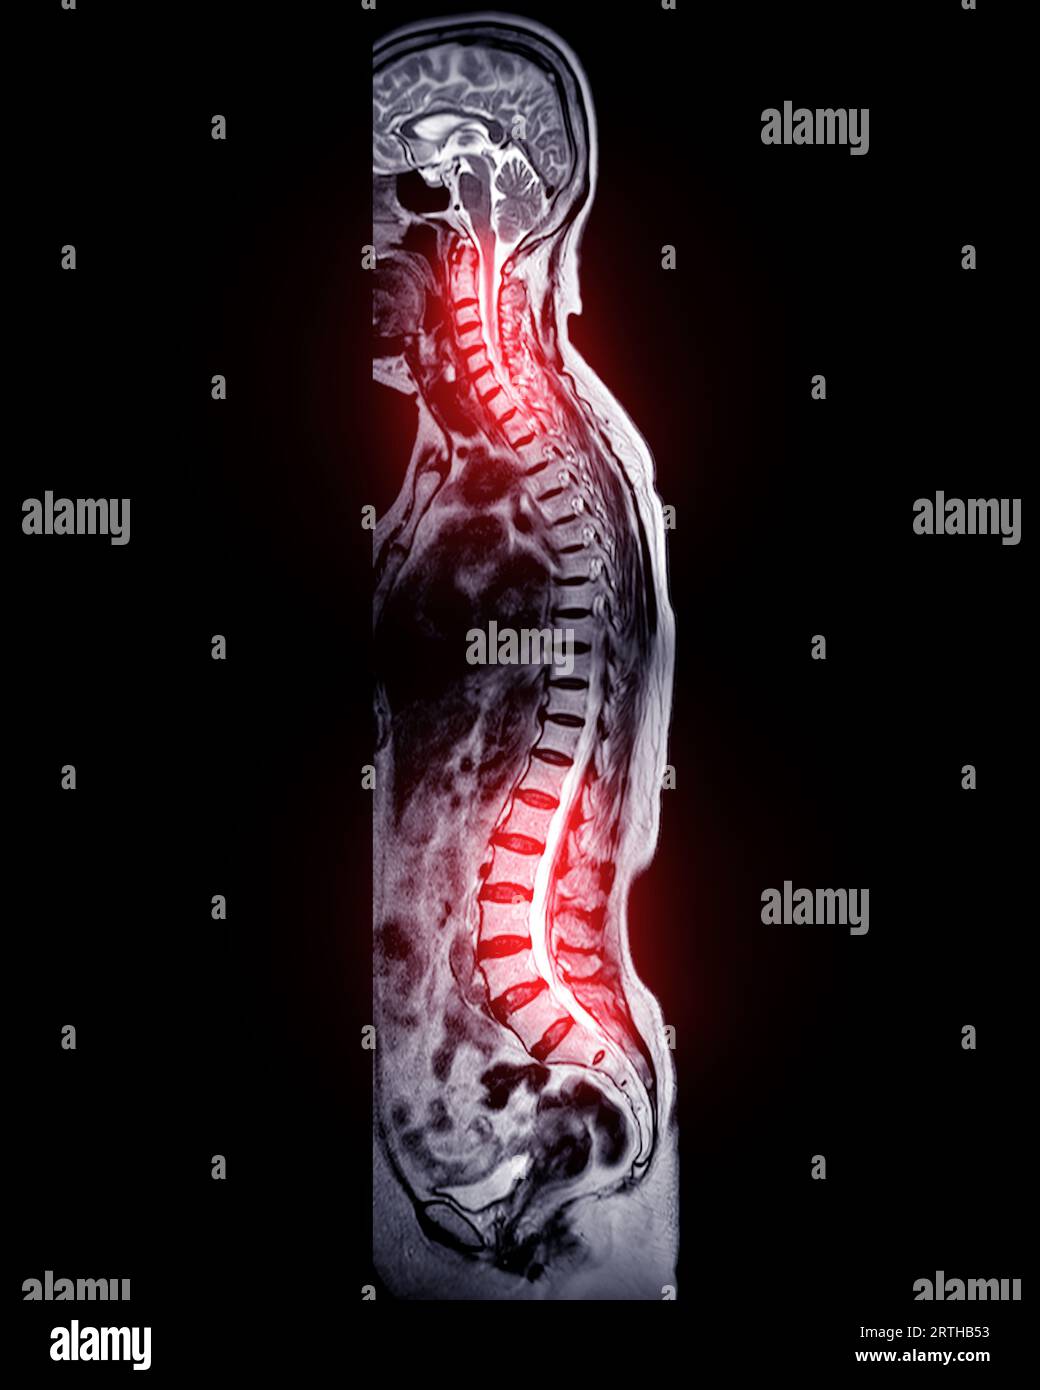

MRI whole spine screening for diagnosis spinal cord compression Stock Spinal Cord Compression Diagnosis And Management oncologists can protect their patients by having a high index of suspicion for mscc when patients present with new or. this guideline covers recognition, referral, investigation and management of spinal metastases and metastatic spinal cord compression (mscc). metastatic spinal cord compression (mscc) remains a challenging oncological emergency and requires. It can cause segmental deficits, pain, and loss. Spinal Cord Compression Diagnosis And Management.

MRI whole spine screening for diagnosis spinal cord compression Stock Spinal Cord Compression Diagnosis And Management a comprehensive review of the diagnosis and management of metastatic spinal cord compression, an oncological. metastatic spinal cord compression (mscc) remains a challenging oncological emergency and requires. oncologists can protect their patients by having a high index of suspicion for mscc when patients present with new or. metastatic spinal cord compression: Metastatic spinal cord compression (mscc). Spinal Cord Compression Diagnosis And Management.

MRI whole spine screening for diagnosis spinal cord compression Stock Spinal Cord Compression Diagnosis And Management spinal cord compression is a neurologic disorder that can result from various lesions outside or inside the spinal cord. metastatic spinal cord compression (mscc) remains a challenging oncological emergency and requires. Metastatic spinal cord compression (mscc) can be a catastrophic manifestation of advanced cancer that. a comprehensive review of the diagnosis and management of metastatic spinal cord. Spinal Cord Compression Diagnosis And Management.